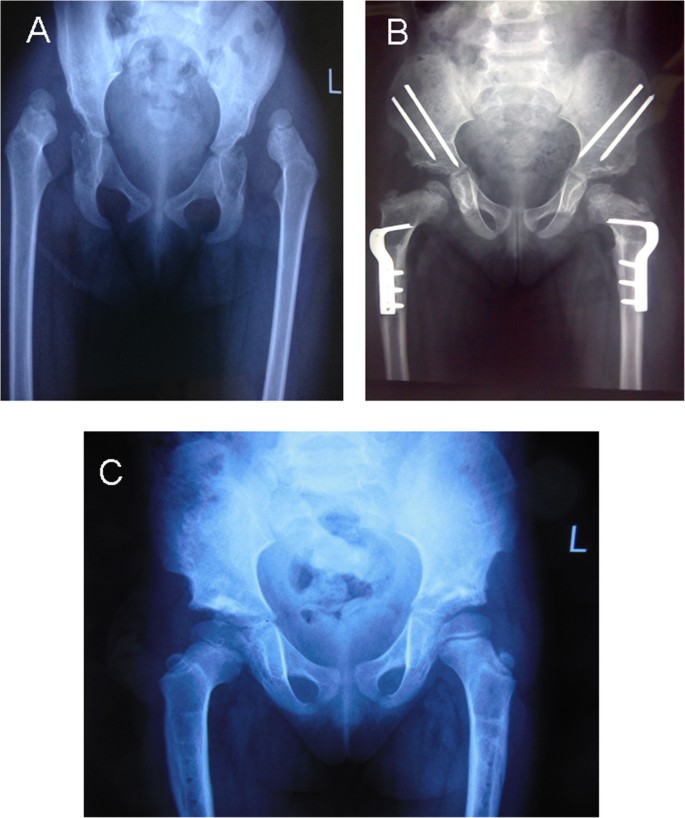

In the present study, we reviewed the outcomes of the one-stage operation for treatment of DDH in 864 hips in children older than 18 months. The McKay and Severin classifications were used to evaluate the clinical and radiographic results, respectively. We showed that 79.4% of good or excellent outcomes were obtained for clinical functional evaluation according to the McKay classification. For radiographic outcomes, 732 hips (84.7%) were classified as good or excellent according to the Severin classification after a mean follow up of 6.2 years. The results are similar to those in other reports [7, 29, 30]. It has been widely reported that AVN of the femoral head is still a severe complication after treatment of DDH. Our results showed that 27.4% of all hips had a poor outcome according to the Kalamchi and MacEwen classification. Previous studies have shown that sufficient femoral shortening and appropriate position of the hip spica might avoid AVN [21, 23]. In the present study, sufficient femoral shortening and stable reduction during the operation were required. After operation, 45° abduction and 30° flexion of the hip was immobilized for 6 weeks. Multiple logistic regression analysis showed that age at surgery and Tonnis grade were risk factors for AVN and poor McKay classification. For poor Severin classification, only age at surgery was a risk factor. These data support those of other researchers [7, 22]. In the present study, good Severin classification showed good clinical outcome in the young and middle groups. However, patients in the older group with poor radiographic outcome after Chiari osteotomy presented with good function of the hip. Some older patients who underwent Steel osteotomy obtained good Severin classification but poor clinical outcome. Furthermore, we failed in 21% of our cases in McKay scores, but failure analysis shows that the majorities of poor scores of McKay were in older patients. These results suggested that age at surgery was an important risk factor for clinical outcome. It is important that walking-age children with DDH should be diagnosed early and treated by one-stage operation for a satisfactory outcome (Figure 2).

shows X-ray in a unilateral DDH, before therapy and at the follow up examination. A. Female patient aged 2.1 years with left DDH. Plain X-ray AP view. B. Plain X-ray AP view 1.6 years after one-stage operation, showing good containment of the femoral head. C. AP view 4.5 years postoperatively with excellent clinical and radiographic outcomes.